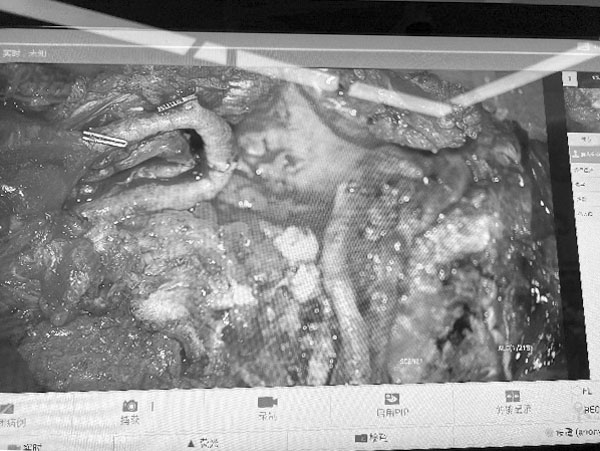

电子显微镜放大10倍后小血管的吻合

游离腹壁下动脉穿支皮瓣自体组织重建术(Deep Inferior Epigastric Perforator Flap,DIEP)是一种利用患者自身腹部皮肤、脂肪及血管进行乳房重建的显微外科手术。该技术通过显微外科手段将腹壁下动脉穿支血管与胸壁血管吻合,实现组织存活,具有创伤小、保留腹直肌功能的特点。其技术特点包括:在显微镜下完成精细血管吻合,确保移植皮瓣的血供;供区损伤小,仅切取腹部脂肪及皮肤,完整保留腹直肌结构,术后恢复更快;重建乳房形态自然持久,触感与外形接近真实乳房,避免了假体相关的包膜挛缩等问题;同时实现腹部整形与乳房重建的双重效果。

DIEP手术代表着自体组织乳房重建的技术高点,其核心在于显微镜下完成细小血管吻合,使离体皮瓣恢复供血并塑形为对称的乳房形态。这一过程需以精准稳定的显微外科技术为支撑,与整形外科理念实现深度融合,二者的协同,是操作成败的关键。